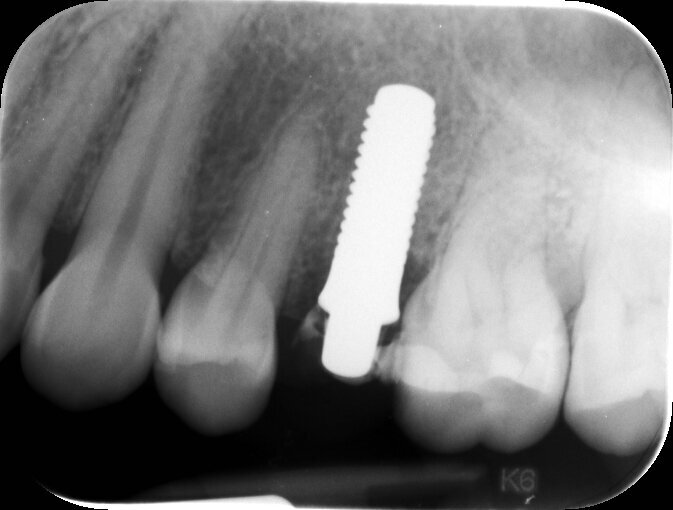

Paziente di sesso femminile di 32 anni, si presenta alla nostra osservazione con la frattura coronale in senso verticale del 2.5 non trattabile con altre terapie (Fig. 1). L’elemento precedentemente recuperato mediante terapia endodontica e successiva ricostruzione diretta in resina composita ha subito un trauma involontario che ne ha causato la frattura verticale sino al terzo radicolare, come evidenzia il radiogramma endorale (Fig. 2) rendendo superflua una ulteriore indagine 3D.

Fig. 2_Rx endorale eseguita con centratore, si evidenzia una buona disponibilità ossea periradicolare. Non si ascrivono alterazioni radicolari.

Fig. 5_Rx di controllo post operatoria con provvisorio in situ, serve per stabilire la posizione dell’impianto in tempo post chirurgico e per valutare se vi è del residuo cementizio al di sotto della corona provvisoria.